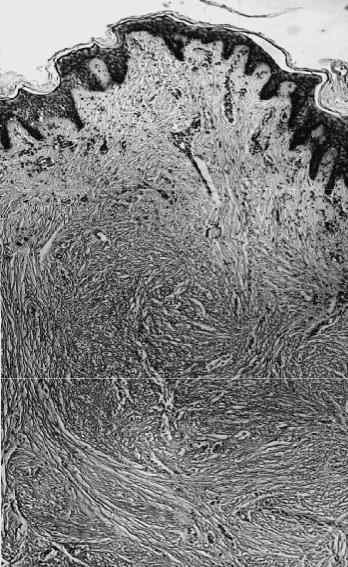

Келоидные рубцы (рис. 72) имеют иные микроскопические особенности

среди обширных полей грубоволокнистой соединительной ткани располага- ются так называемые «узлы роста» /16/. Они состоят из множества функцио- нально активных фибробластов, вокруг которых располагаются многочислен- ные толстые короткие коллагеновые пучки, напоминающие остеоидные балки.

Рис. 72. В микропрепарате ке- лоидный рубец под аутотранс- плантатом после глубокого ожога; в «узле роста» — многочисленные фибробласты; три месяца после аутопластики (окраска толуидино- вым синим, × 40)